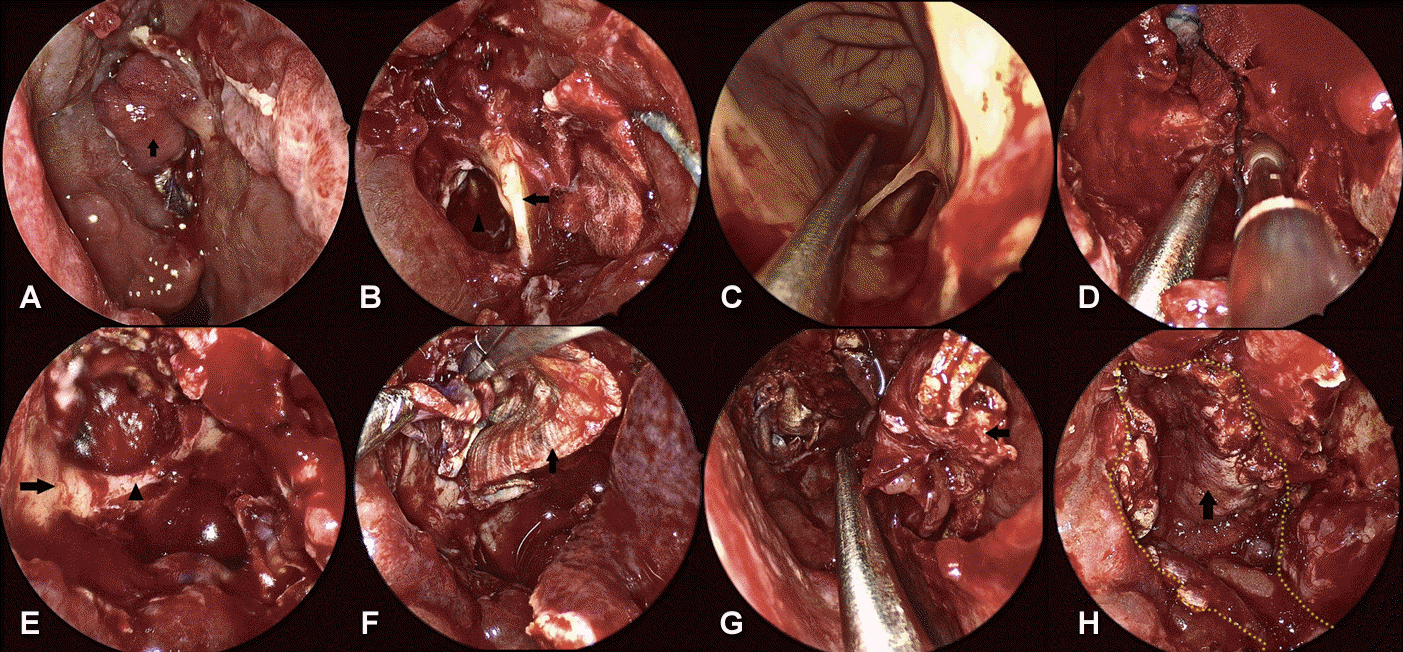

Skull base defect was partially covered with ipsilateral mucosal flap from the previous tertiary hospital under the intraoperative endoscopic view (Fig. 3A). Active CSF leakage was identified along the inferior border of Onodi cell. Septal cartilage graft and abdominal fat graft were covering the 10 mm-sized skull base defect after the meticulous dissection of the previous septal mucosal flap (Fig. 3B). After removal of compacted materials with the conception of the debridement, the frontal horn of right lateral ventricle was exposed through the cerebromalatic basal frontal lobe (Fig. 3C). With temporary gauze packing, inflamed mucosa of sphenoid sinus and Onodi cell border was peeled off and drilled to secure clear, smooth, and non-infected bone margin where the new pedicled nasoseptal flap could be engrafted (Fig. 3D). During these procedures, optic nerve canal was identified and saved (Fig. 3E). Skull base defect was reconstructed with the double-layered autologous fascia lata from right thigh in fashion of buttress (Fig. 3F). Contralateral nasoseptal flap extending to nasal floor was elevated to obtain the sufficient length and size to cover the skull base defect (Fig. 3G and H). Margin of nasoseptal flap was anchored with Surgicel (Ethicon, J&J Surgical Technologies, Arlington, TX, USA) followed by the applying DURASEAL (COVIDIEN, Waltham, MA, USA) and nasal cavity packing with absorbable materials.

Fig. 3.

Intraoperative endoscopic views (0º endoscope). A: Previous mucosal flap (arrow). B: Previous septal cartilage graft (arrow). 10 mm skull base defect on the left (arrowhead). C: Lumen of lateral ventricle. D: Gauze packing at the defect opening and onodi cell border being drilled. E: Drilled margin of skull base defect (arrow) and optic nerve canal (arrowhead). F: Autologous fascia lata (arrow). G and H: Contralateral nasoseptal flap (arrow). Yellow dots stand for contour of the flap margin.